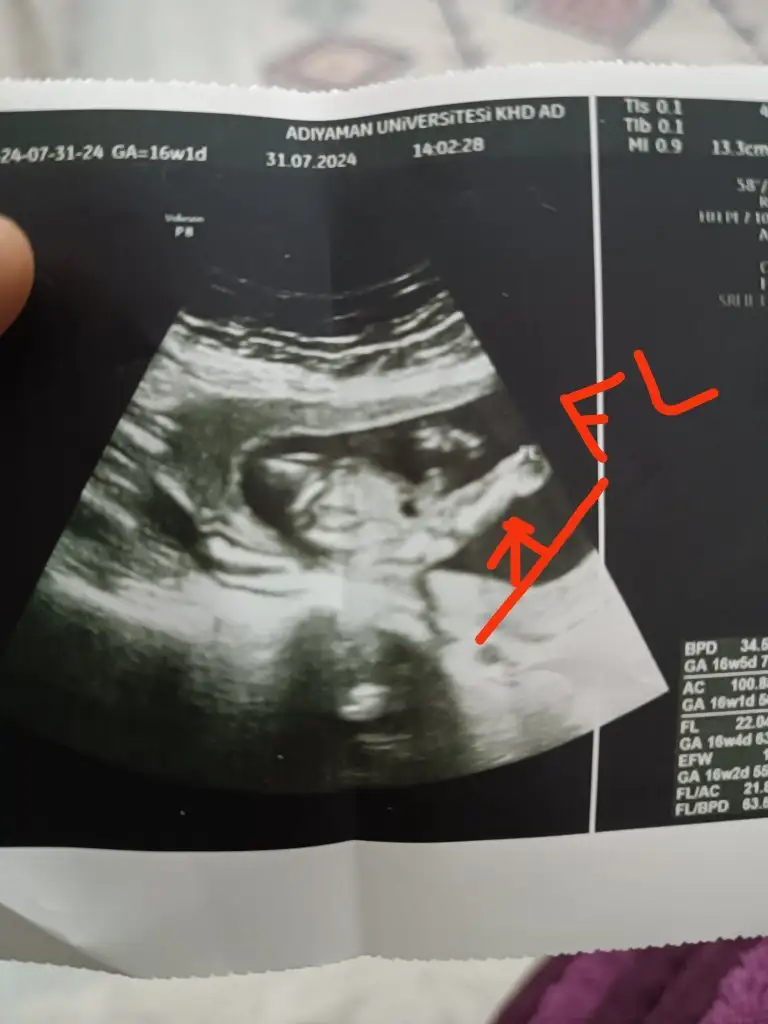

Bacak arasını acabaKızlar bugun kontrole gittim devlete bir umut kız der diye oda erkek dedibirde bu usg fotosunu verdi ne neresidir bir türlü çıkaramadım bir sizde bakın yaa ölçtüğü kısıma fl demiş benim bildiğim fl de boydan boya uyluk kemiğinin ölçümü

Canım o işaretlediğin yer bacak benceKızlar bugun kontrole gittim devlete bir umut kız der diye oda erkek dedibirde bu usg fotosunu verdi ne neresidir bir türlü çıkaramadım bir sizde bakın yaa ölçtüğü kısıma fl demiş benim bildiğim fl de boydan boya uyluk kemiğinin ölçümü